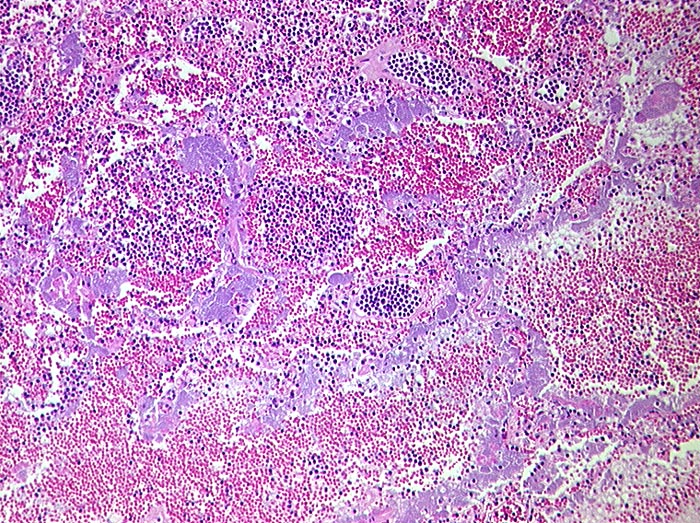

Infarktoide areaktive Pneumonie bei Lymphom

Blaue Bakterienrasen entlang der Alveolarsepten. Intraalveoläre Hämorrhagien. Die kleinen dunklen Zellen entsprechen Lymphominfiltraten. Ein reaktives entzündliches Infiltrat fehlt.

T-Zell Lymphom mit leukämischer Ausschwemmung.

Lymphom seit 3 Jahren. Massive Leukozytose.